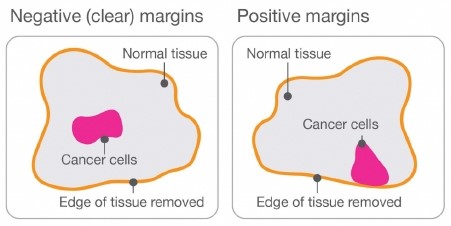

Understanding Surgical Margins In Breast Cancer

cancer margins surgical margin affect understanding ferster verywell

Breast-conserving Surgery – Torbay And South Devon NHS Foundation Trust

www.torbayandsouthdevon.nhs.uk

community.macmillan.org.uk

community cancer breast margins macmillan online results

What Do Margins Mean In Breast Cancer / Resection Margin Wikipedia

dcis margins breastcancernow carcinoma ductal situ tumor stage